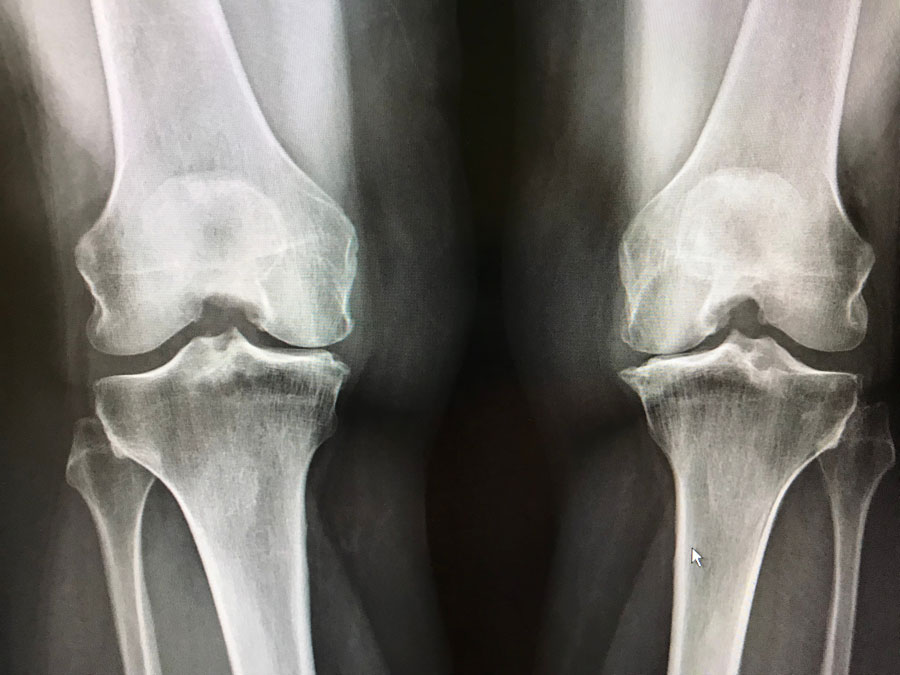

Utilización de la atención médica y mortalidad en personas con artrosis en el Reino Unido

Las personas con osteoartrosis tuvieron mayores tasas de consultas de médicos de cabecera, ingresos hospitalarios y mortalidad por todas las causas que variaron entre los sitios conjuntos. Br J Gen Pract,, 10 de julio de 2023